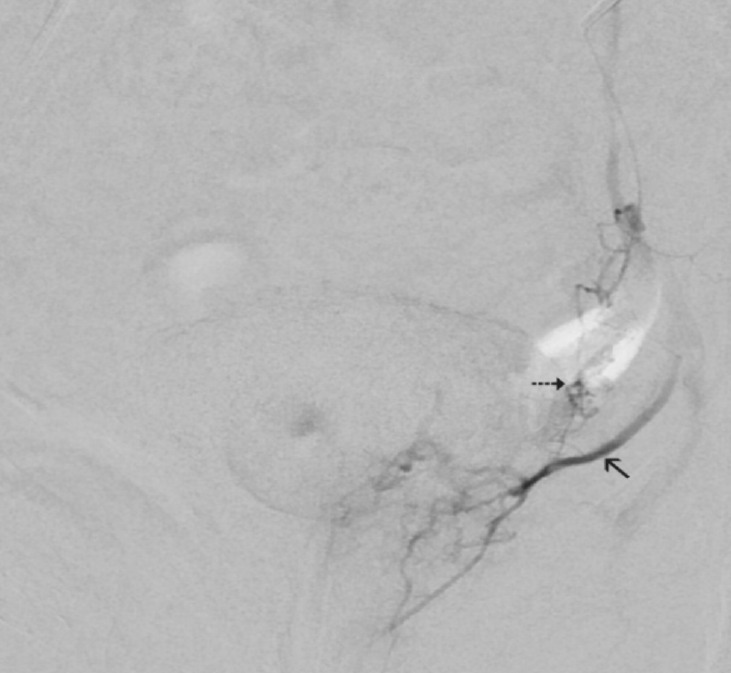

Prostatic artery (PA) origination from a common trunk with the superior vesical artery (SVA) is a frequent cause of technical difficulties in PA catheterization for PA embolization (PAE). These difficulties, which substantially increase the operative time, radiation dose, cost, and technical failure rate of PAE, can often be overcome by the utilization of a steerable microcatheter (MC) with a tip that can be manually adjusted at an angle that optimally conforms to the shape and origin of the common vesicoprostatic trunk. Adjunctive techniques that can be applied when the steerable MC fails to engage the PA include: 1) the protective temporary embolization of the SVA so that a permanent embolic can be redirected into the PA; 2) PAE via collaterals between superior vesical branches and the PA; and 3) embolization from a proximal position of the MC near the PA orifice to exploit preferential flow to the PA. In the authors' recent experience, the utilization of a steerable MC with and without adjunctive techniques (in 12 and 23 patients, respectively) resulted in a 35% increase in the technically successful embolization of PAs originating from vesicoprostatic trunks with no significant complications. Familiarization with alternative devices and techniques may substantially improve the technical outcome of PAE in cases with challenging arterial anatomy.